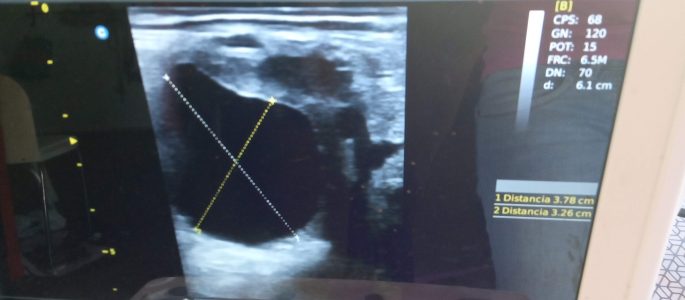

Nuestro equipo está especializado en técnicas de reproducción asistida como la inseminación. Se realiza un seguimiento ecográfico del ciclo de la yegua con el fin de determinar el mejor momento para su inseminación o cubrición por monta natural si así lo prefieres.

En primer lugar, se realiza una evaluación visual y ecográfica del aparato reproductor, así como una evaluación vaginal.

Una vez la yegua ha sido inseminada o cubierta, se podrá realizar su diagnóstico de gestación a partir de los 14 días. También se recomienda una

segunda visita en torno a los 2 meses para asegurar de que la gestación continúa de forma correcta. Además es un buen momento para determinar el sexo del feto.

Si quieres un seguimiento de la gestación más exhaustivo, se recomienda realizar ecografías en torno a los 5, 7 y 9 meses de gestación coincidiendo con la vacunación frente a rinoneumonitis (EHV).